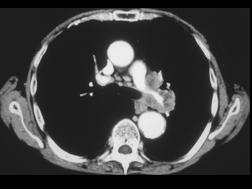

男,59岁,咳嗽,咳痰,痰中带血2月余,CT检查如图,请选出最可能的诊断 ( )A、肺炎B、肺错构瘤C、中央型肺癌D、矽肺E、肺结核

问题 男,59岁,咳嗽,咳痰,痰中带血2月余,CT检查如图,请选出最可能的诊断 ( )

选项 A、肺炎 B、肺错构瘤 C、中央型肺癌 D、矽肺 E、肺结核

答案 C